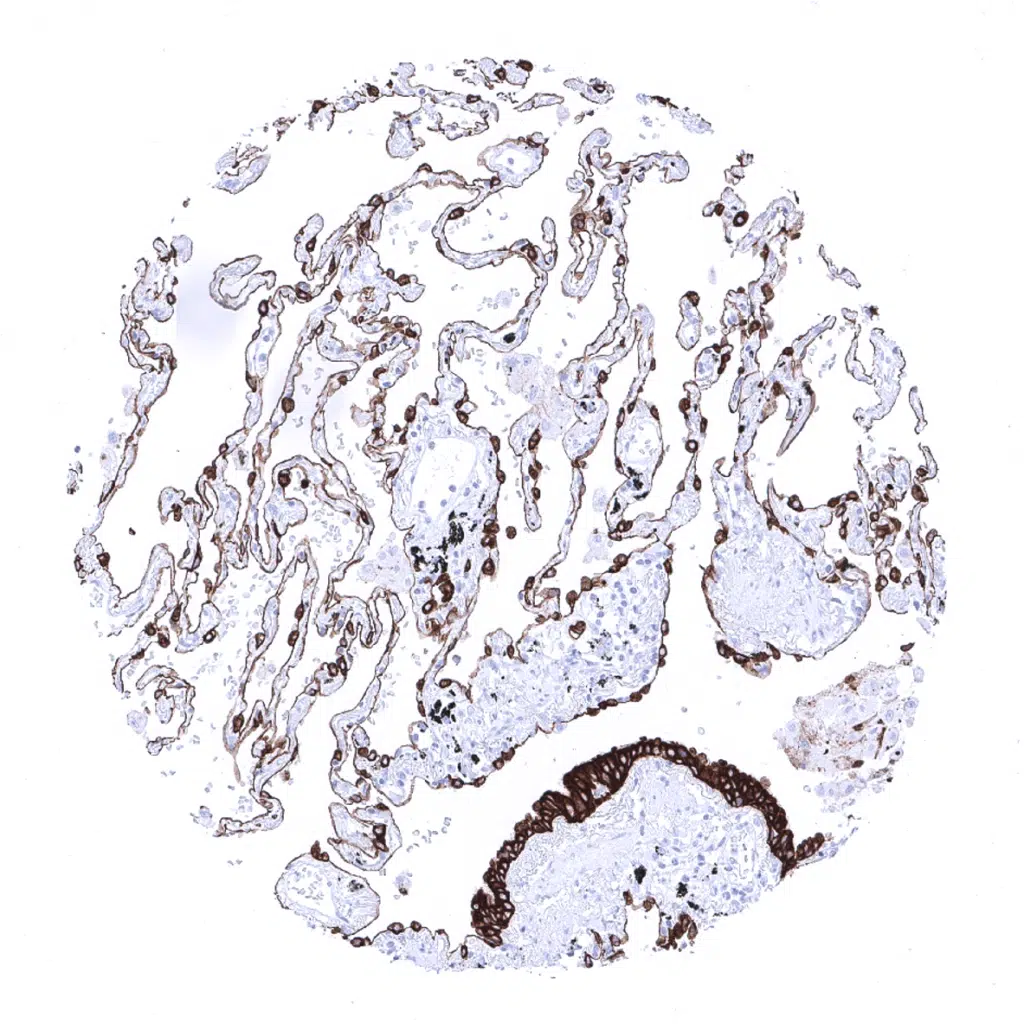

Lung- Pneumocytes show a moderate Cytokeratin 19 staining.